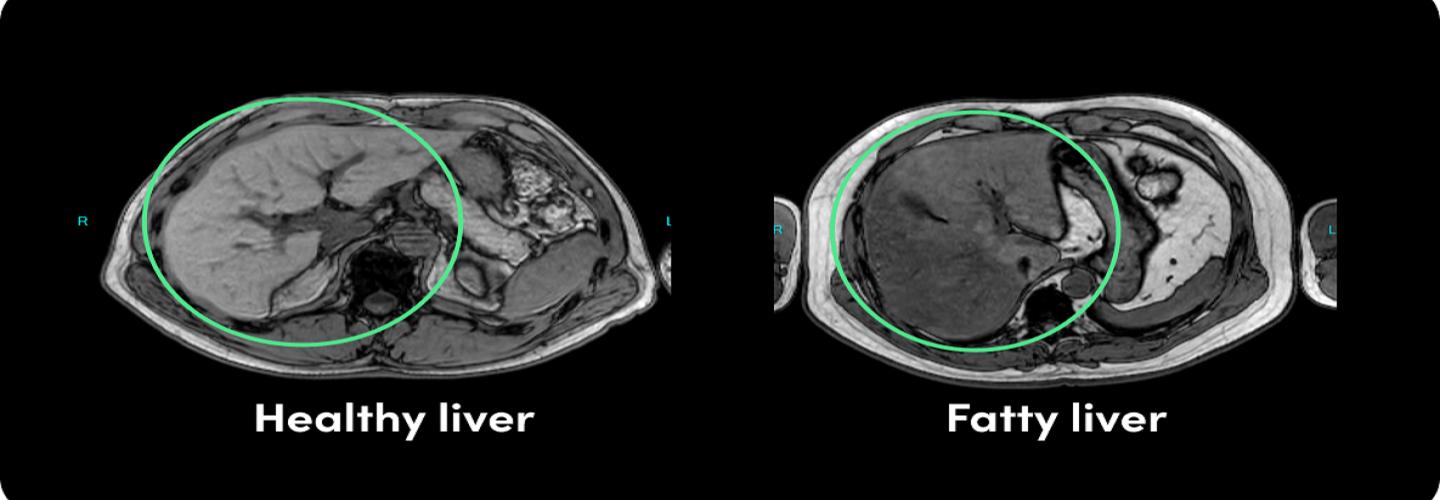

Advance your journey to proactive health at Prenuvo Pasadena, located in the vibrant South Lake Business District. We're committed to shifting healthcare from reactive treatment to preventive well-being for the Pasadena and San Gabriel Valley communities. Our whole body MRI offers a comprehensive MRI scan that serves as a vital tool for early cancer detection and effective cancer screening. Prenuvo's radiation-free, and non-invasive scan can identify hundreds of conditions, including stage 1 cancers and aneurysms, often before symptoms arise. Experience the future of diagnostics at Prenuvo Pasadena, where our unique system of hardware, software, and AI delivers exceptional imaging detail for the earliest possible detection of abnormalities.